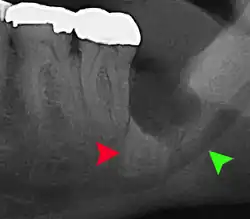

| 3D CT of an impacted wisdom tooth adjacent the inferior alveolar nerve prior to removal of wisdom tooth | |

If the tooth cannot be assessed with clinical exam alone, the diagnosis is made using either a panoramic radiograph or cone-beam CT. Where unerupted wisdom teeth still have eruption potential several predictors are used to determine the chance of the teeth becoming impacted. The ratio of space between the tooth crown length and the amount of space available, the angle of the teeth compared to the other teeth are the two most commonly used predictors, with the space ratio being the most accurate. Despite the capacity for movement into early adulthood, the likelihood that the tooth will become impacted can be predicted when the ratio of space available to the length of the crown of the tooth is under 1.[5]: 141

Long-term complications can include periodontal complications such as bone loss on the second molar following wisdom teeth removal. Bone loss as a complication after wisdom teeth removal is uncommon in the young but present in 43% of those of 25 years of age or older.[23] Injury to the inferior alveolar nerve resulting in numbness or partial numbness of the lower lip and chin has reported rates that vary widely from 0.04% to 5%.[23] The largest study is from a survey of 535 oral and maxillofacial surgeons in California, where a rate of 1:2,500 was reported.[26]

Coronectomy is a procedure where the crown of the impacted wisdom tooth is removed, but the roots are intentionally left in place. It is indicated when there is no disease of the dental pulp or infection around the crown of the tooth, and there is a high risk of inferior alveolar nerve injury.[32]